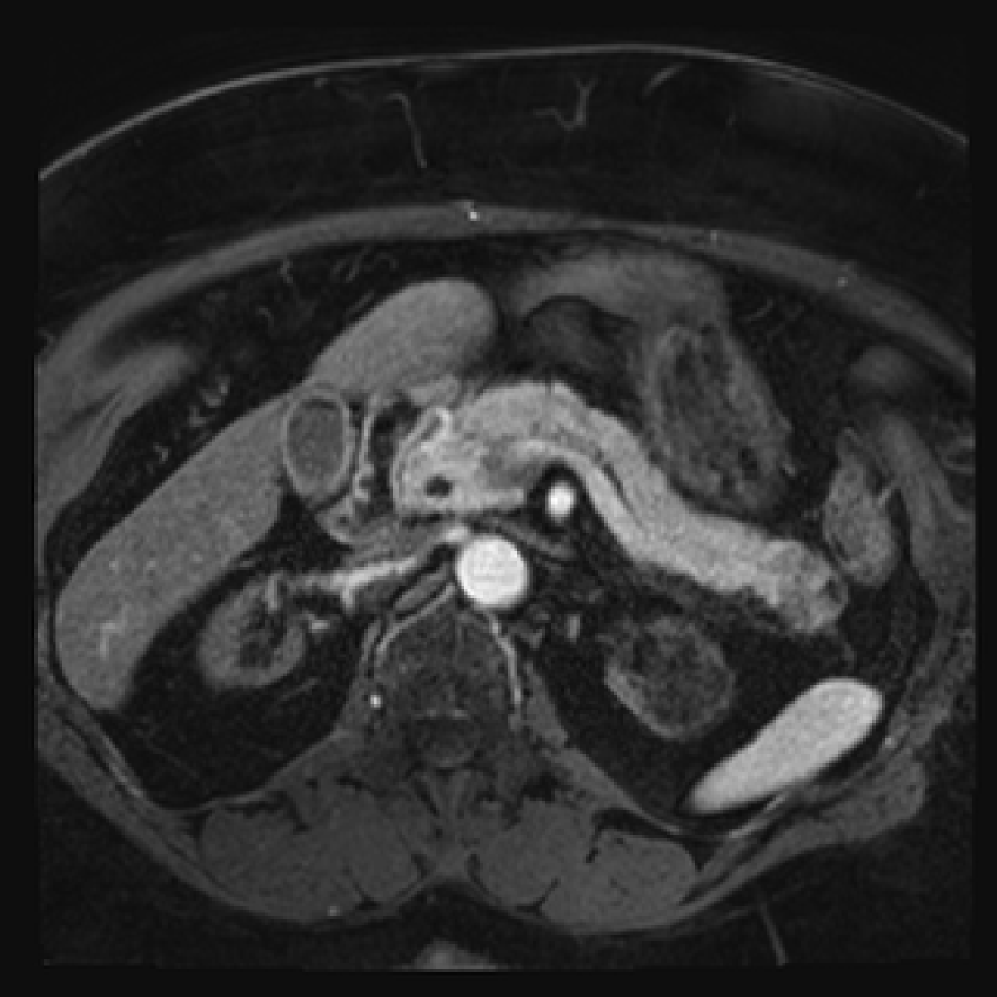

Accurate pancreas segmentation is a critical prerequisite for precise cyst analysis and classification. Recently, we developed PanSegNet [zhang2025large], a novel segmentation architecture incorporating linear self-attention layers [zhang2022dynamic] within the nnUNet framework [isensee2021nnu] to enhance global information modeling capabilities while maintaining computational efficiency (Fig. 1). PanSegNet demonstrated exceptional segmentation performance across both T1W and T2W modalities, achieving mean dice scores of 86.817.30% and 89.626.38%, respectively (Table 1, Fig. 2b-c). This performance significantly exceeded that of Swin-UNETR [hatamizadeh2021swin], one of the most used state-of-the-art transformer-based medical segmentation models, which achieved dice scores of 79.091.40% and 76.290.66% for T1W and T2W, respectively (). In this study, we integrated PanSegNet into our Cyst-X engine along with a classifier for risk prediction. In Section 2.2, we show that the choice of segmentation model affects the classification results. The performance advantage of PanSegNet was consistent across all seven medical centers, demonstrating robust generalization despite variations in imaging protocols and equipment (Table 1). This cross-institutional reliability is particularly important for clinical applications, where model performance must remain consistent regardless of imaging site or acquisition parameters.

Each patient was categorized into one of these three ground truth classes: no risk/control, IPMN low-risk, or IPMN high-risk. To evaluate variability in image acquisition, we applied uniform manifold approximation and projection (UMAP) to image quality indicators, revealing distinct clustering patterns by imaging center and slice thickness. This heterogeneity reflects real-world clinical variability, enhancing the dataset’s generalizability while presenting technical challenges for model development. Fig. 6 shows examples of low-grade, high-grade, and cancer developing IPMNs from the Cyst-X dataset.